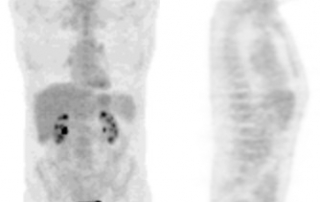

Imagerie évaluation de la réponse :

Classement en fin de traitement : rémission complète

Le traitement a été réalisé selon le programme de soin initial